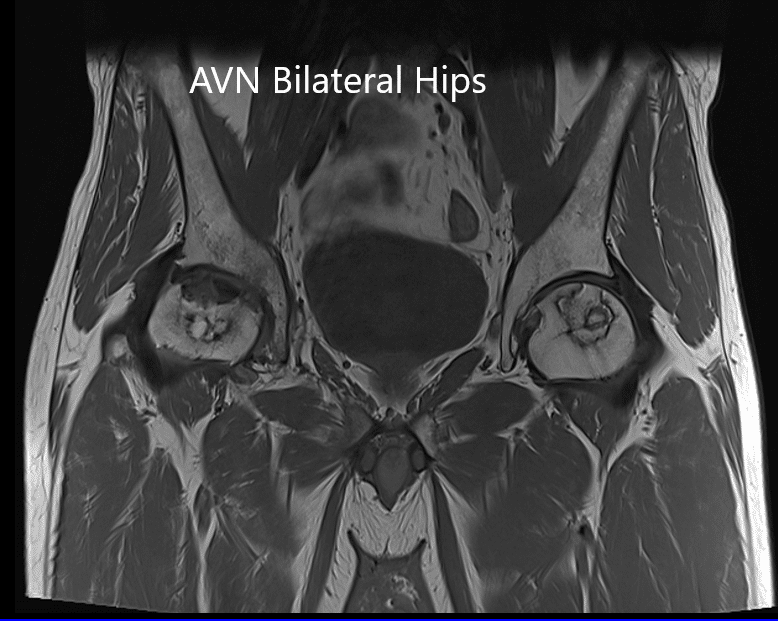

MRI suggested marked signal attenuation of bilateral femoral heads. There was a collapse of the right head and precollapse stage 2a of the left hip.

MRI showing bilateral femoral head AVN in T1WI